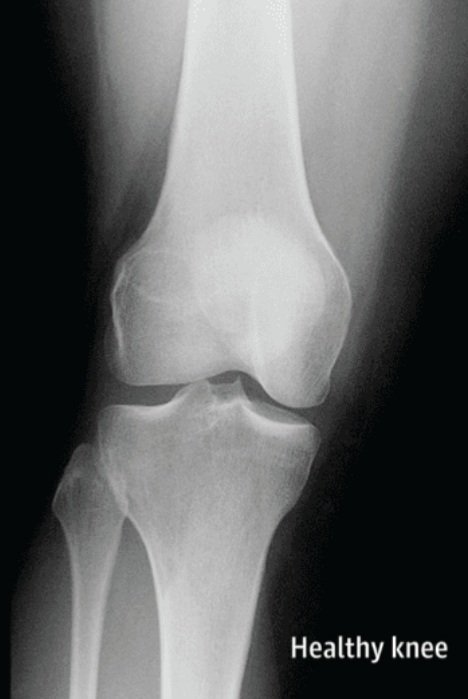

- ركبة سليمة👇